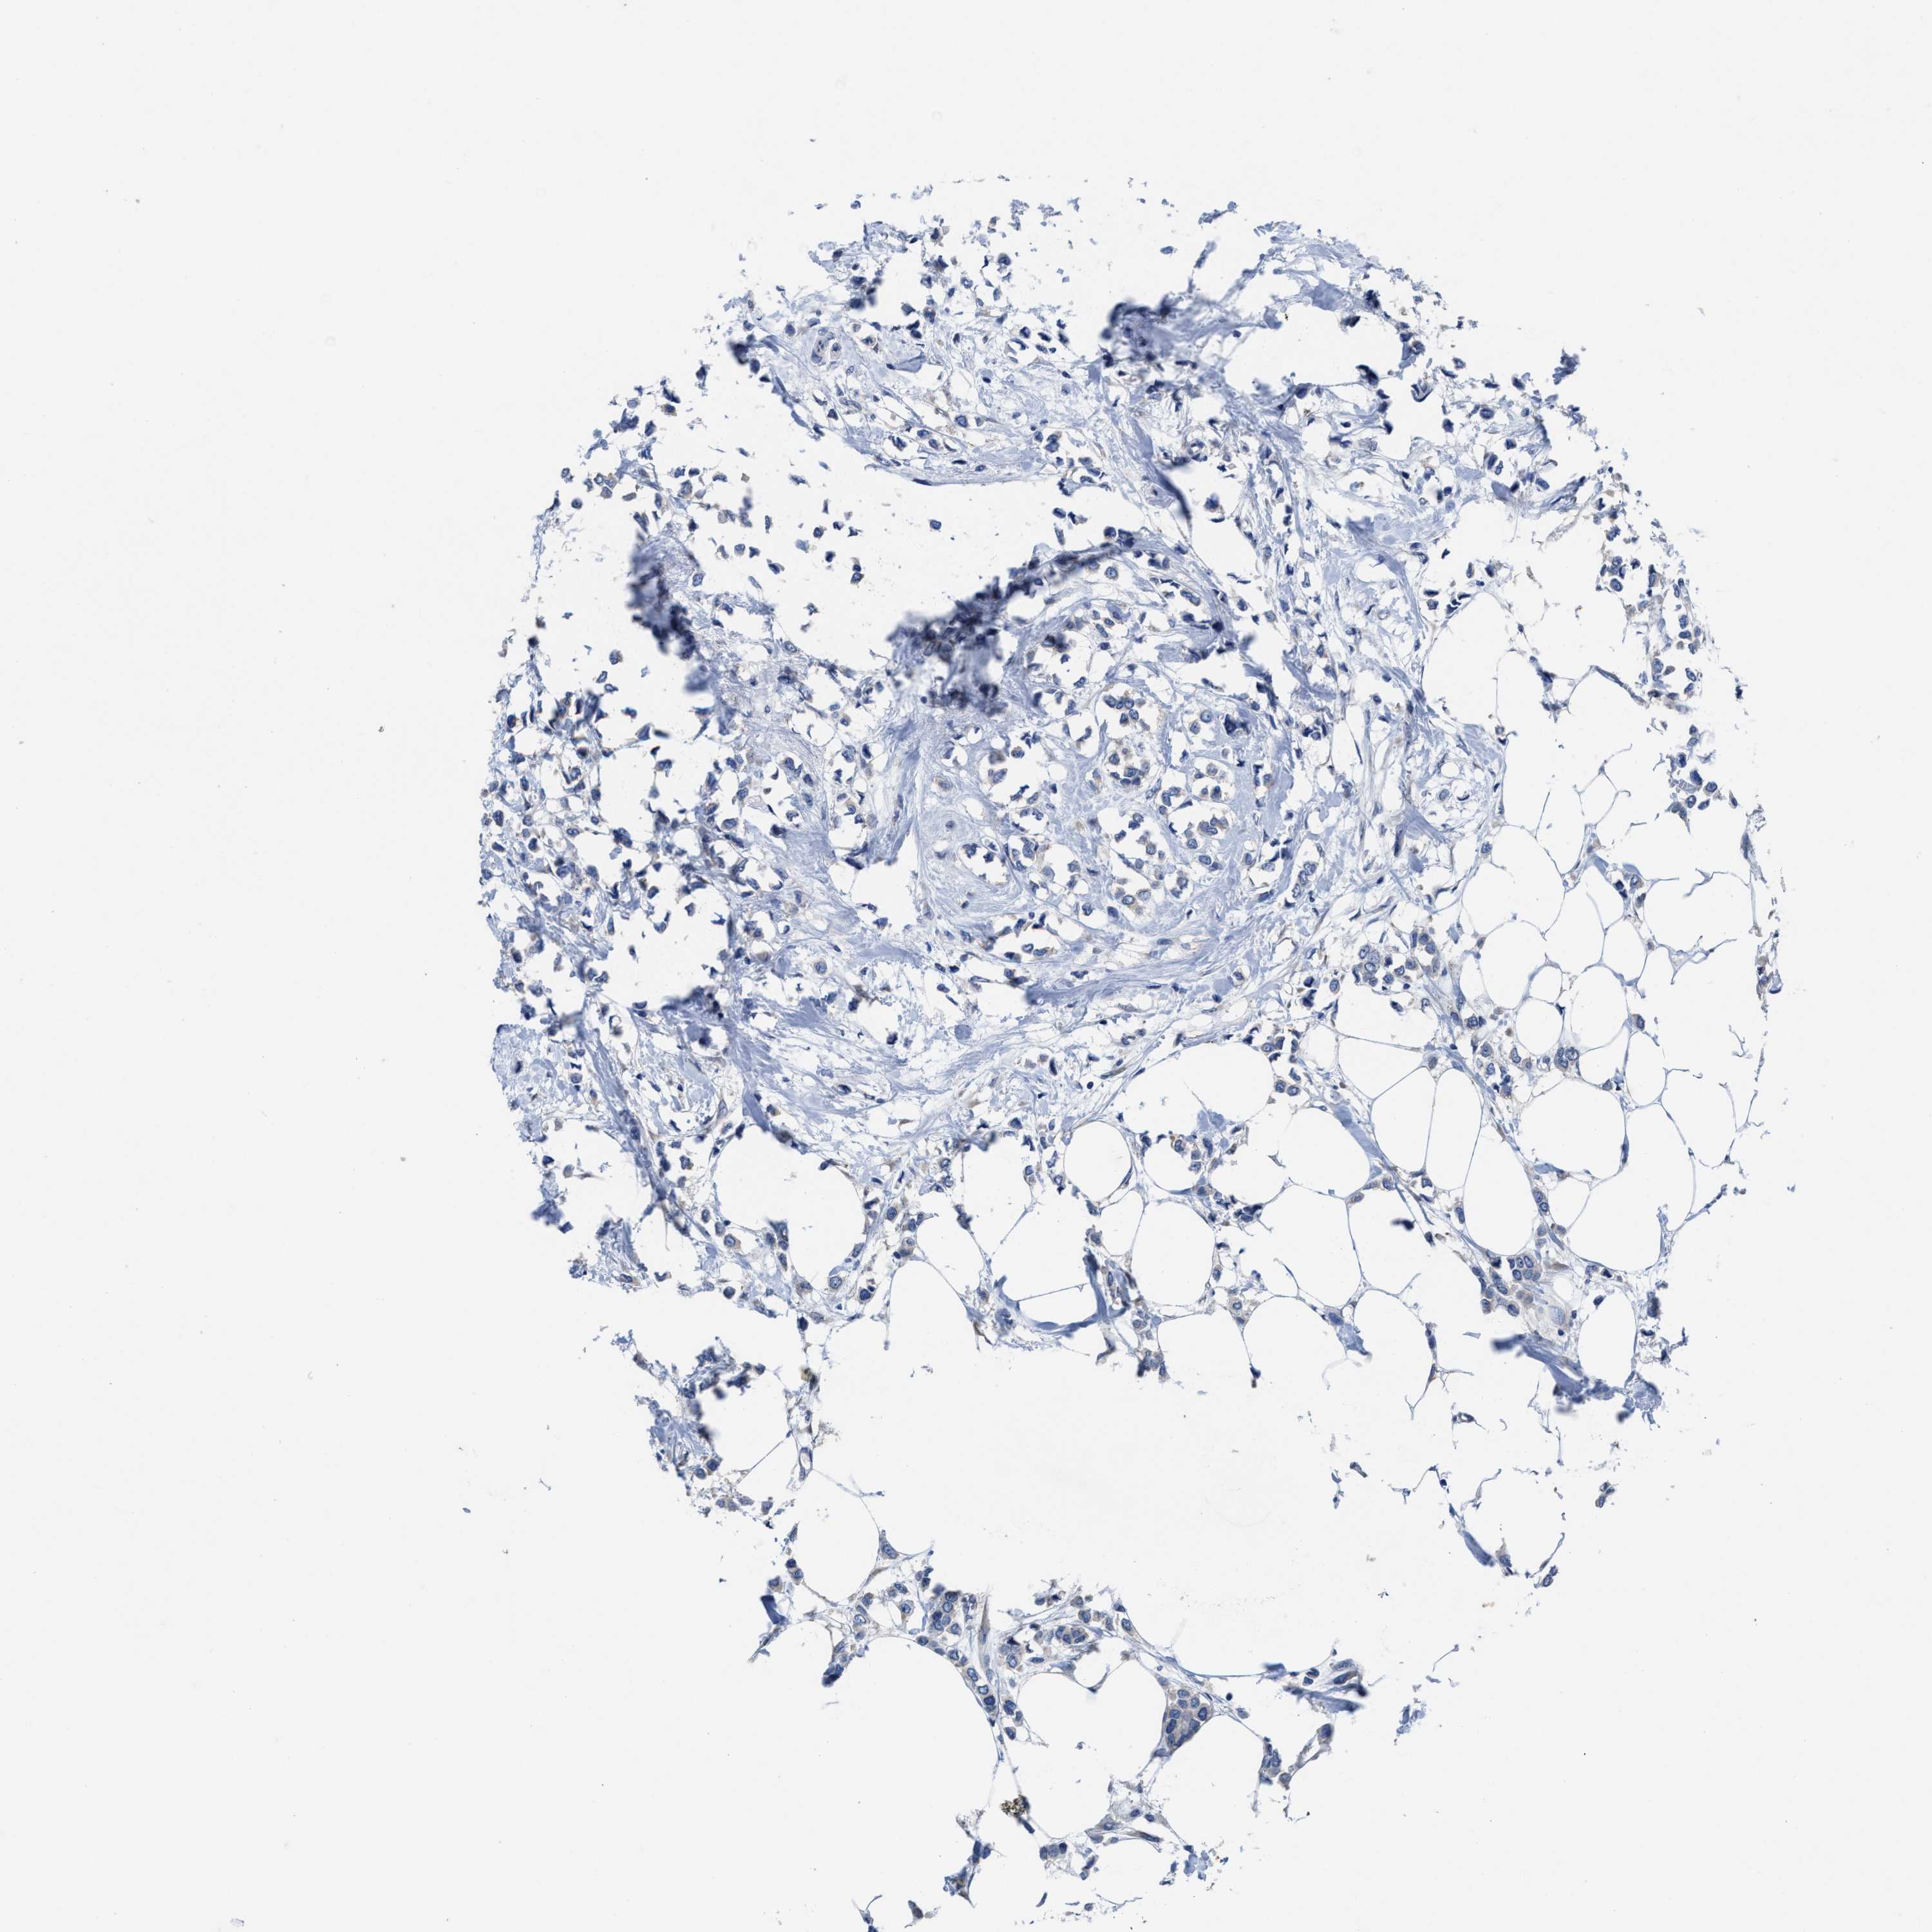

BRCA TCGA BRCA VALIDATION PROTEIN EXPRESSION